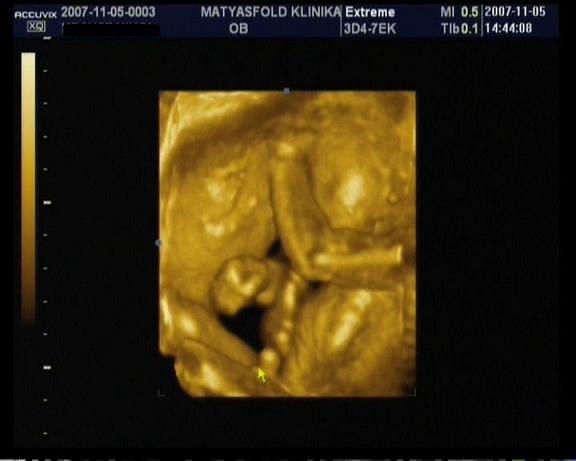

a 7ik héttől már látható a szívcső lüktetése, 8ik héttől a gerincoszlop és már akár testmozgások is láthatók! Ez nem jelenti azt, hogy feltétlenül mozogni is fog az uh alatt, valamikor ő is pihen!

Persze ezekhez szakértő szem szükséges, tehát az orvos mindent látni fog, és el fog mondani!!